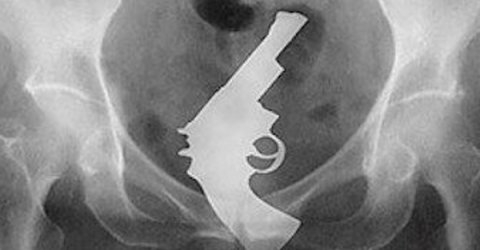

The craziest science experiments ever conducted (11 Photos)